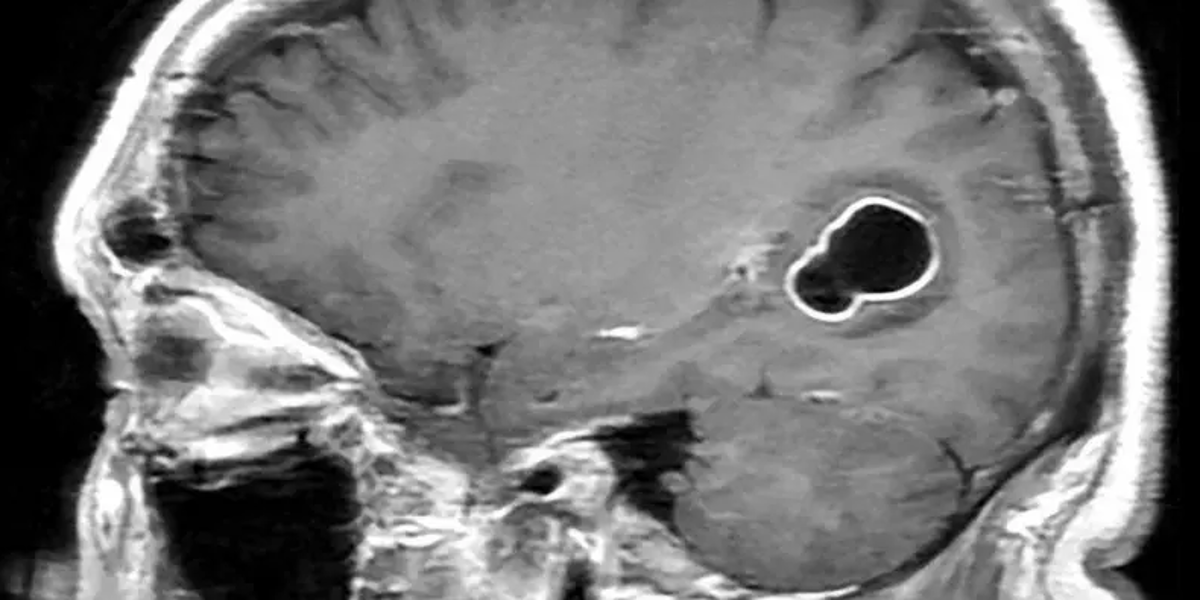

Imágenes de escáneres cerebrales

Fuente de la imagen, American Journal of Case Reports

Pie de foto,

Estas imágenes permitieron detectar la presencia de las larvas de tenia en el cerebro del paciente.

Al realizarle tomografías, los médicos encontraron la presencia de numerosos quistes en el cerebro que, según luego comprobaron con estudios posteriores, en realidad eran larvas de tenia que se habían instalado en su cerebro y que eran las causantes de una infección conocida como neurocisticercosis.